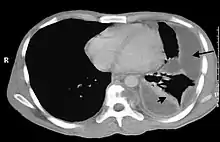

Якщо результати нечіткі, можна зробити комп'ютерну томографію грудної клітки.